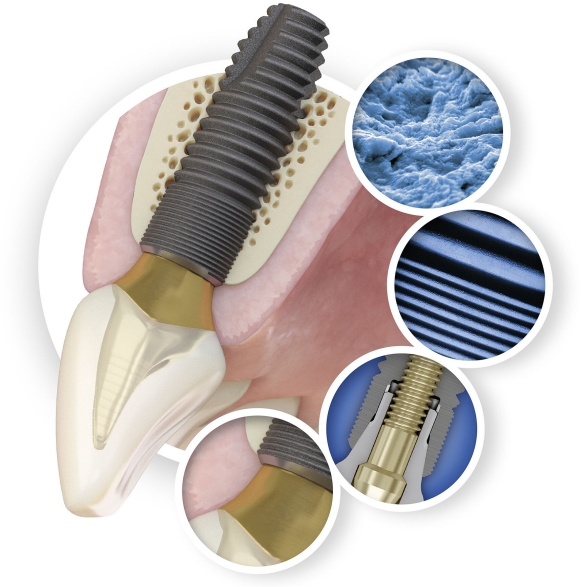

The maintenance of marginal bone is the foundation for dental implant success and a key factor for the esthetic outcome.

When working with Astra Tech Implant System EV the unparalleled marginal bone maintenance helps you deliver: